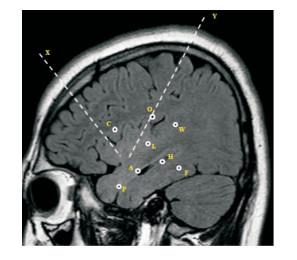

電極植入方案為個體化設計,根據患者頭皮腦電圖間歇期放電、發作期放電,發作期癥狀學,病變的結構成像和代謝成像,和語言、記憶功能優勢半球等情況進行具體設計。若假設致癇區為顳葉(圖 1),電極通常覆蓋的結構為:杏仁核、海馬(前部、后部)、內嗅區、梭狀回,顳極,顳上回、顳中回、顳下回的中部、后部。若假設致癇區涉及顳葉外腦結構,電極覆蓋的區域需根據假設的致癇區網絡、鑒別網絡、病變結構邊界以及皮層功能區定位的需求進行設計(圖 2)。電極通常覆蓋的結構為:島頂、島前小葉、島后小葉,島葉蓋部(側裂上、下),額眶區,顳頂枕交界區。若假設致癇區為雙側性的,對主要懷疑致癇區的一側半球電極需系統覆蓋(如上),對側半球懷疑的致癇區電極需重點覆蓋(主要在顳葉)。

P:顳極, A:顳中回前部-杏仁核, H:顳中回中部-海馬前部, F:顳下回后部-梭狀回, L:顳上回中部-島后長回, W:顳上回后部, C:中央下回前部-上環島溝前部, O:頂蓋-上環島溝后部, X:額中回-島前小葉, Y:頂上小葉-島后小葉.右半球未顯示, H′:顳中回中部-海馬前部, V′':顳上回前部-島頂, L′:顳上回中部-島前長回